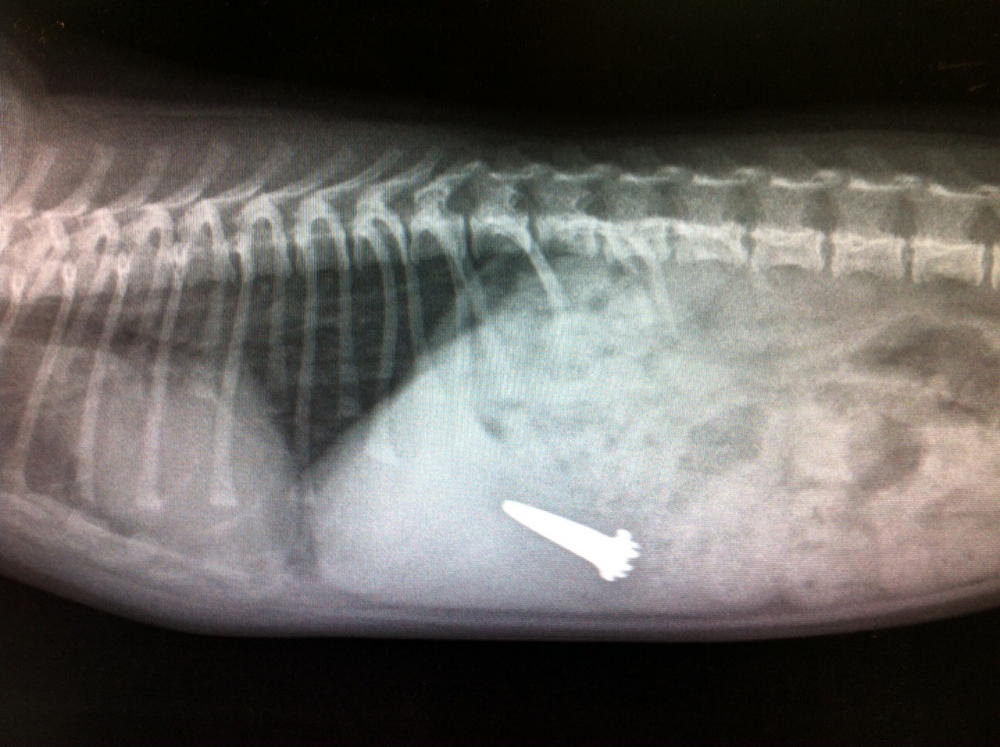

תמונות מהמרפאה